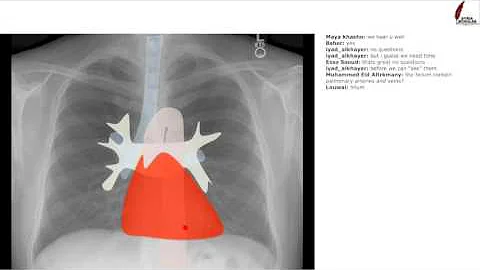

The ABCDE's to reading a chest xray! A: Airway. Look at the airway. It should be midline. Tumors, tension pneumothorax, large ...